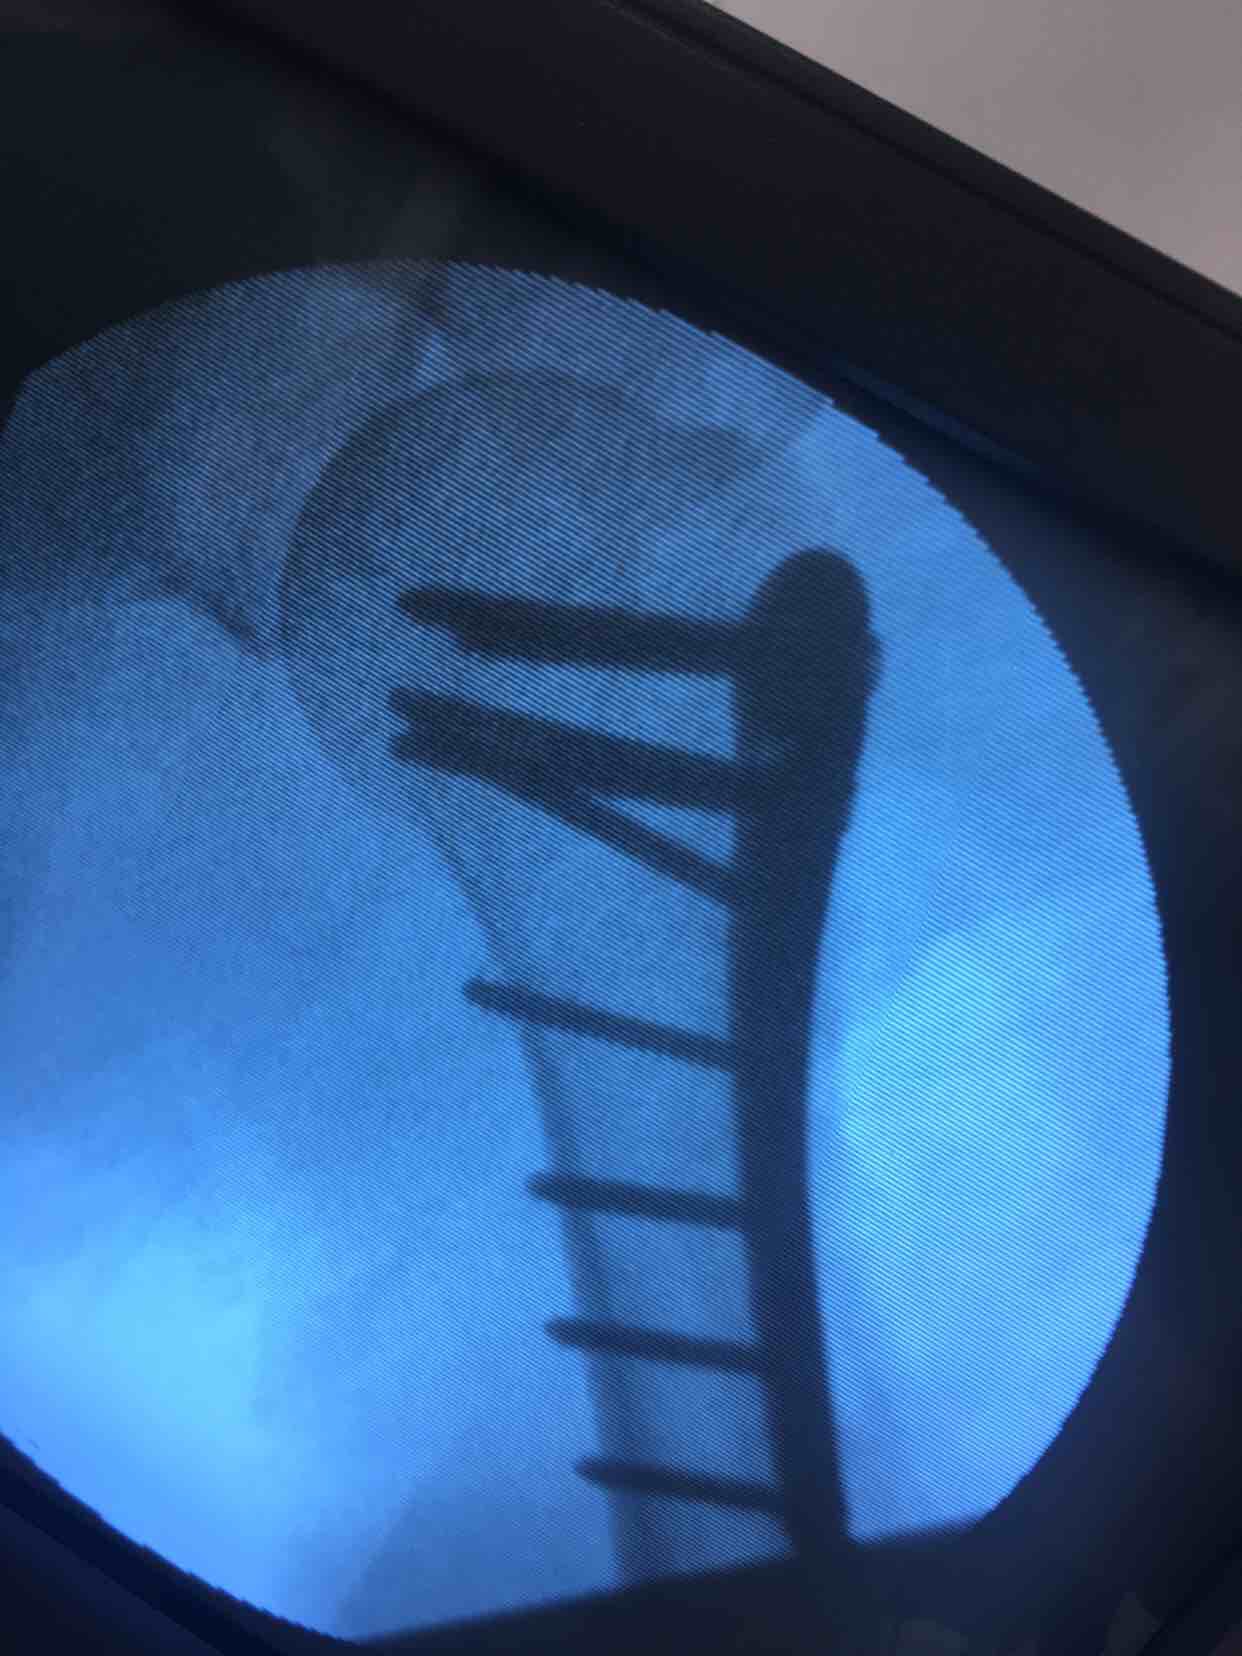

肱骨外科颈粉碎性骨折(切复内固定术)

诊断:肱骨外科颈粉碎性骨折(右)完善术前准备,在臂丛麻醉下行切复内固定术,选肱骨近端锁定钛板,保持稳定性及早期功能锻炼。术后抗炎,消肿等处理。

手术最大优势尽可能解剖复位,保障骨折稳定,早期功能锻炼,避免肩肘腕综合征,骨折移位风险发生。